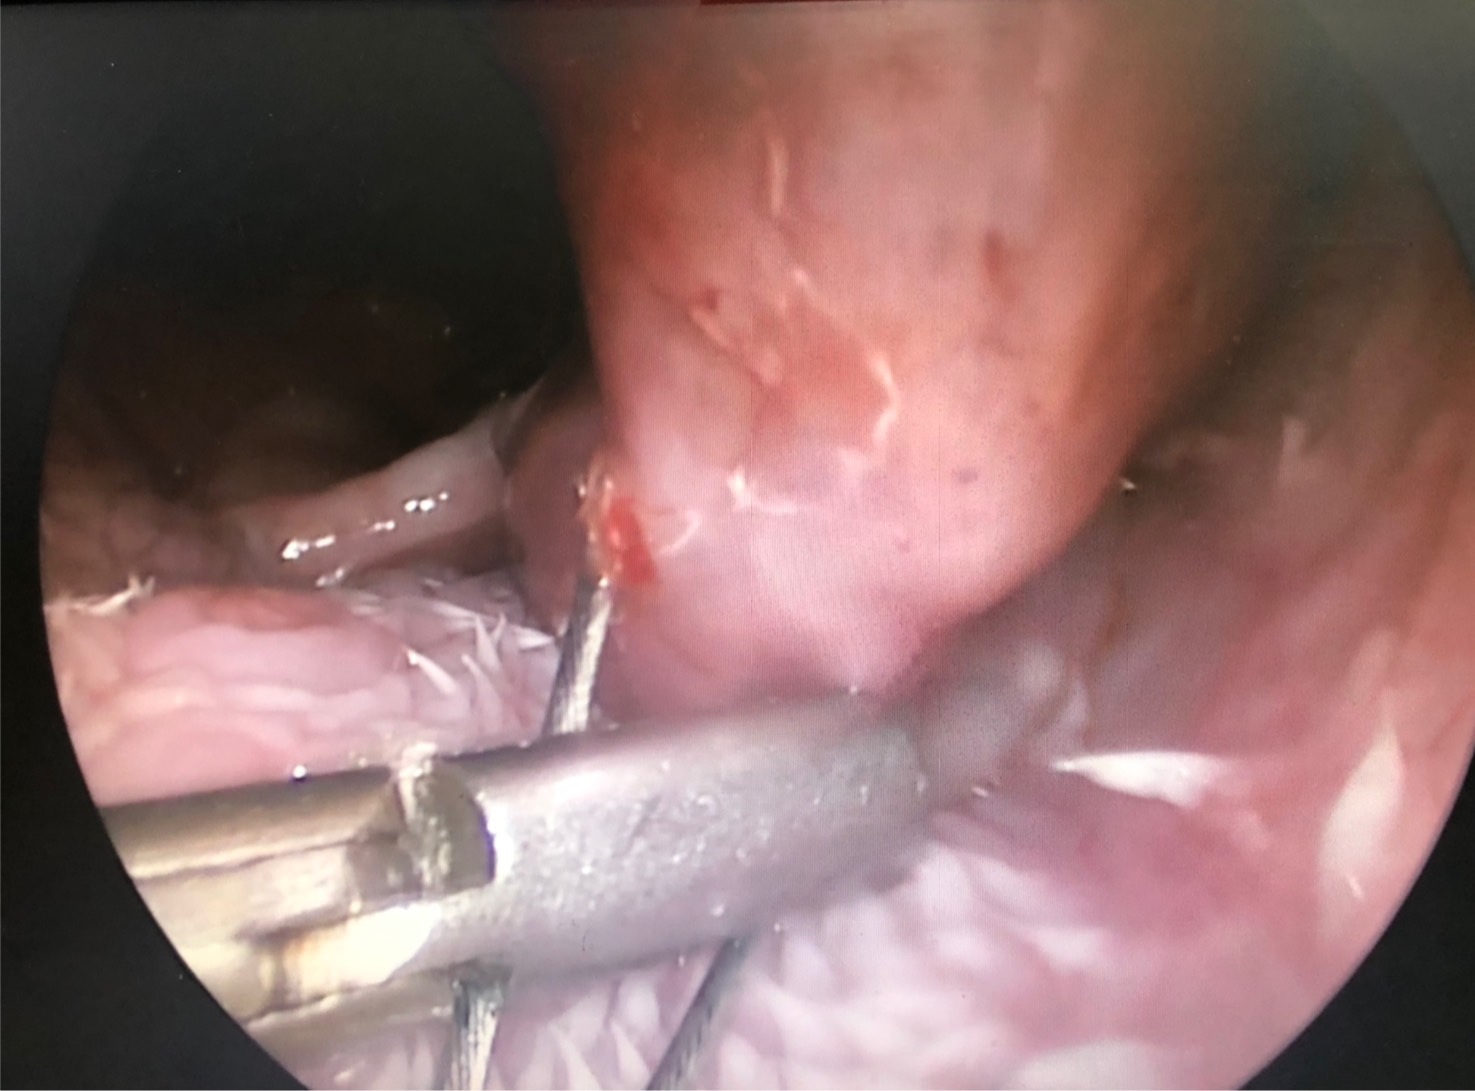

初步懷疑呼吸道阻塞,安排電腦斷層掃描/內視鏡探查手術,精準定位病灶團塊的範圍,利用內視鏡輔助套環套住團塊後經電燒將可見到範圍盡量切除乾淨。

同時將切除的團塊做病理切片。術後三個月到現在沒有症狀也沒有復發。

病理報告為嚴重、慢性活躍性、漿細胞及化膿性喉炎,伴隨肉芽組織生成及局部上皮細胞異型性,會厭旁團塊